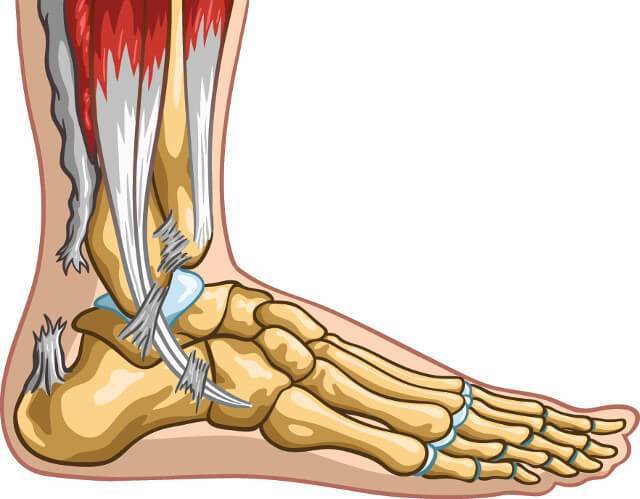

To look for Achilles tendon problems, an examiner checks for pain, swelling, warmth, thickening, or discoloration around the heel and leg. A knot on the back of the leg may be present with Achilles tendon rupture. Most cases of tendinopathy without a rupture can be diagnosed by physical exam and often do not need further testing.